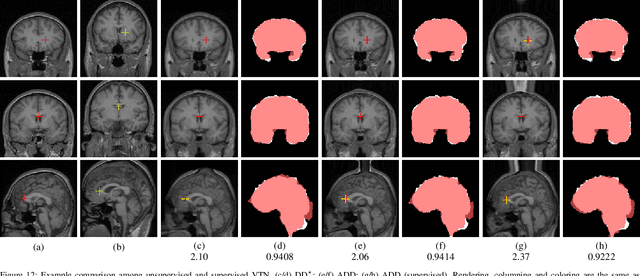

Abstract:3D medical image registration is of great clinical importance. However, supervised learning methods require a large amount of accurately annotated corresponding control points (or morphing). The ground truth for 3D medical images is very difficult to obtain. Unsupervised learning methods ease the burden of manual annotation by exploiting unlabeled data without supervision. In this paper, we propose a new unsupervised learning method using convolutional neural networks under an end-to-end framework, Volume Tweening Network (VTN), to register 3D medical images. Three technical components ameliorate our unsupervised learning system for 3D end-to-end medical image registration: (1) We cascade the registration subnetworks; (2) We integrate affine registration into our network; and (3) We incorporate an additional invertibility loss into the training process. Experimental results demonstrate that our algorithm is 880x faster (or 3.3x faster without GPU acceleration) than traditional optimization-based methods and achieves state-of-the-art performance in medical image registration.